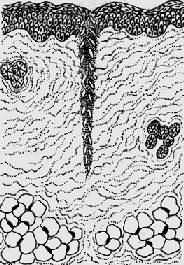

2.二期愈合(healing by second intention) 见于组织缺损较大、创缘不整、哆开、无法整齐对合,或伴有感染的伤口。这种伤口的愈合与一期愈合有以下不同:①由于坏死组织多,或由于感染,继续引起局部组织变性、坏死,炎症反应明显。只有等到感染被控制,坏死组织被清除以后,再生才能开始。②伤口大,伤口收缩明显,从伤口底部及边缘长出多量的肉芽组织将伤口填平。③愈合的时间较长,形成的瘢痕较大(图2-6)。

1.创口大,创缘不整,组织破坏多

2.伤口收缩,炎症反应重

3.肉芽组织从伤口底部及边缘将伤口填平,然后表皮再生

4.愈合后形成疤痕大

图2-6 创伤二期愈合模式图